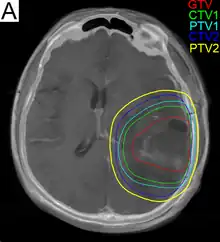

Subsequent to surgery, radiotherapy becomes the mainstay of treatment for people with glioblastoma. It is typically performed along with giving temozolomide.[10] A pivotal clinical trial carried out in the early 1970s showed that among 303 GBM patients randomized to radiation or best medical therapy, those who received radiation had a median survival more than double those who did not.[69] Subsequent clinical research has attempted to build on the backbone of surgery followed by radiation. Whole-brain radiotherapy does not improve when compared to the more precise and targeted three-dimensional conformal radiotherapy.[70] A total radiation dose of 60–65 Gy has been found to be optimal for treatment.[71]